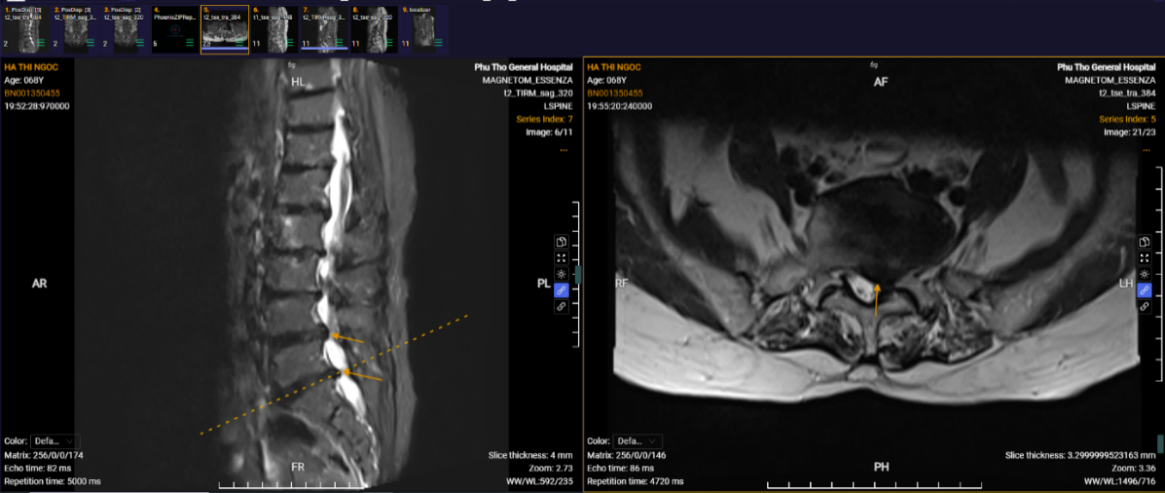

Hình ảnh phim chụp của người bệnh Hà Thị Ngọc khi vào viện.

Hình ảnh phim chụp của người bệnh Hà Thị Ngọc sau phẫu thuật.

Hơn 20 năm chịu đựng những cơn đau lưng hành hạ, phục hồi chỉ sau 10 ngày phẫu thuật là trường hợp của người bệnh Hà Thị Ngọc, trú tại phường Thanh Miếu, tỉnh Phú Thọ. Người bệnh nhập viện trong tình trạng đau thắt lưng kéo dài, đau lan xuống hai chân và cả tay trái, kèm tê bì nhiều. “Có những lúc tôi cảm thấy cơ thể đau nhức như bị hàng nghìn mũi kim châm chích. Dù đã điều trị theo nhiều phương pháp nhưng chỉ đỡ được một thời gian rồi lại đau lại”.